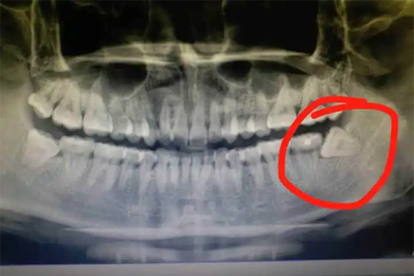

倾斜生长的智齿会持续挤压邻牙牙根,导致前牙拥挤移位或牙根吸收。正畸治疗后的患者可能出现牙齿复发畸形,需通过曲面断层片评估后拔除阻生齿。邻牙已出现明显移位时,可能需联合正畸治疗恢复咬合关系。

长期存在的阻生智齿可能刺激颌骨形成含牙囊肿或角化囊肿,X线可见透射影伴骨质破坏。囊肿增大可导致病理性骨折或神经压迫,需手术摘除囊肿并拔除患牙。术后需定期复查排除复发可能。